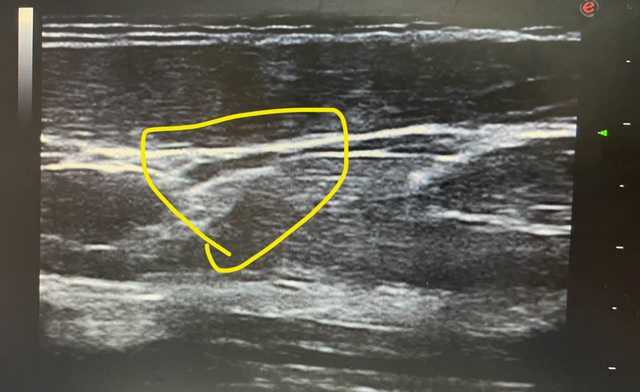

各位好 今天我陪家人去復健科照前臂部位的超音波 醫生看完報告後 說前臂外上髁肌肉拉傷、筋膜剝離 醫生指出超音波圖中有一個白影就是剝離的筋膜 並指出沒有治療方案,醫生也不願意多解釋,只說不能復健,只能等他自己好 想請問板上有人也受過一樣的傷嗎? 是否有較積極的治療方式 我自己在網上找資料也找不到筋膜剝離之類的資料 ——— 附上超音波圖 醫生說黃圈處筋膜跟肌肉分離 https://i.imgur.com/Zx1mcf6.jpg